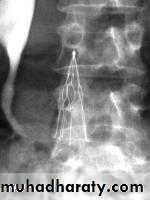

5- Inferior vena cava filter

It reduces pulmonary embolism and is indicated in those patients with recurrent pulmonary emboli while on anti coagulant & for those with DVT who carry a risk of pulmonary embolism but have a contra – indication for anti – coagulation. It is called Greenfield filter.It may prevent pulmonary embolization of the leg clot.